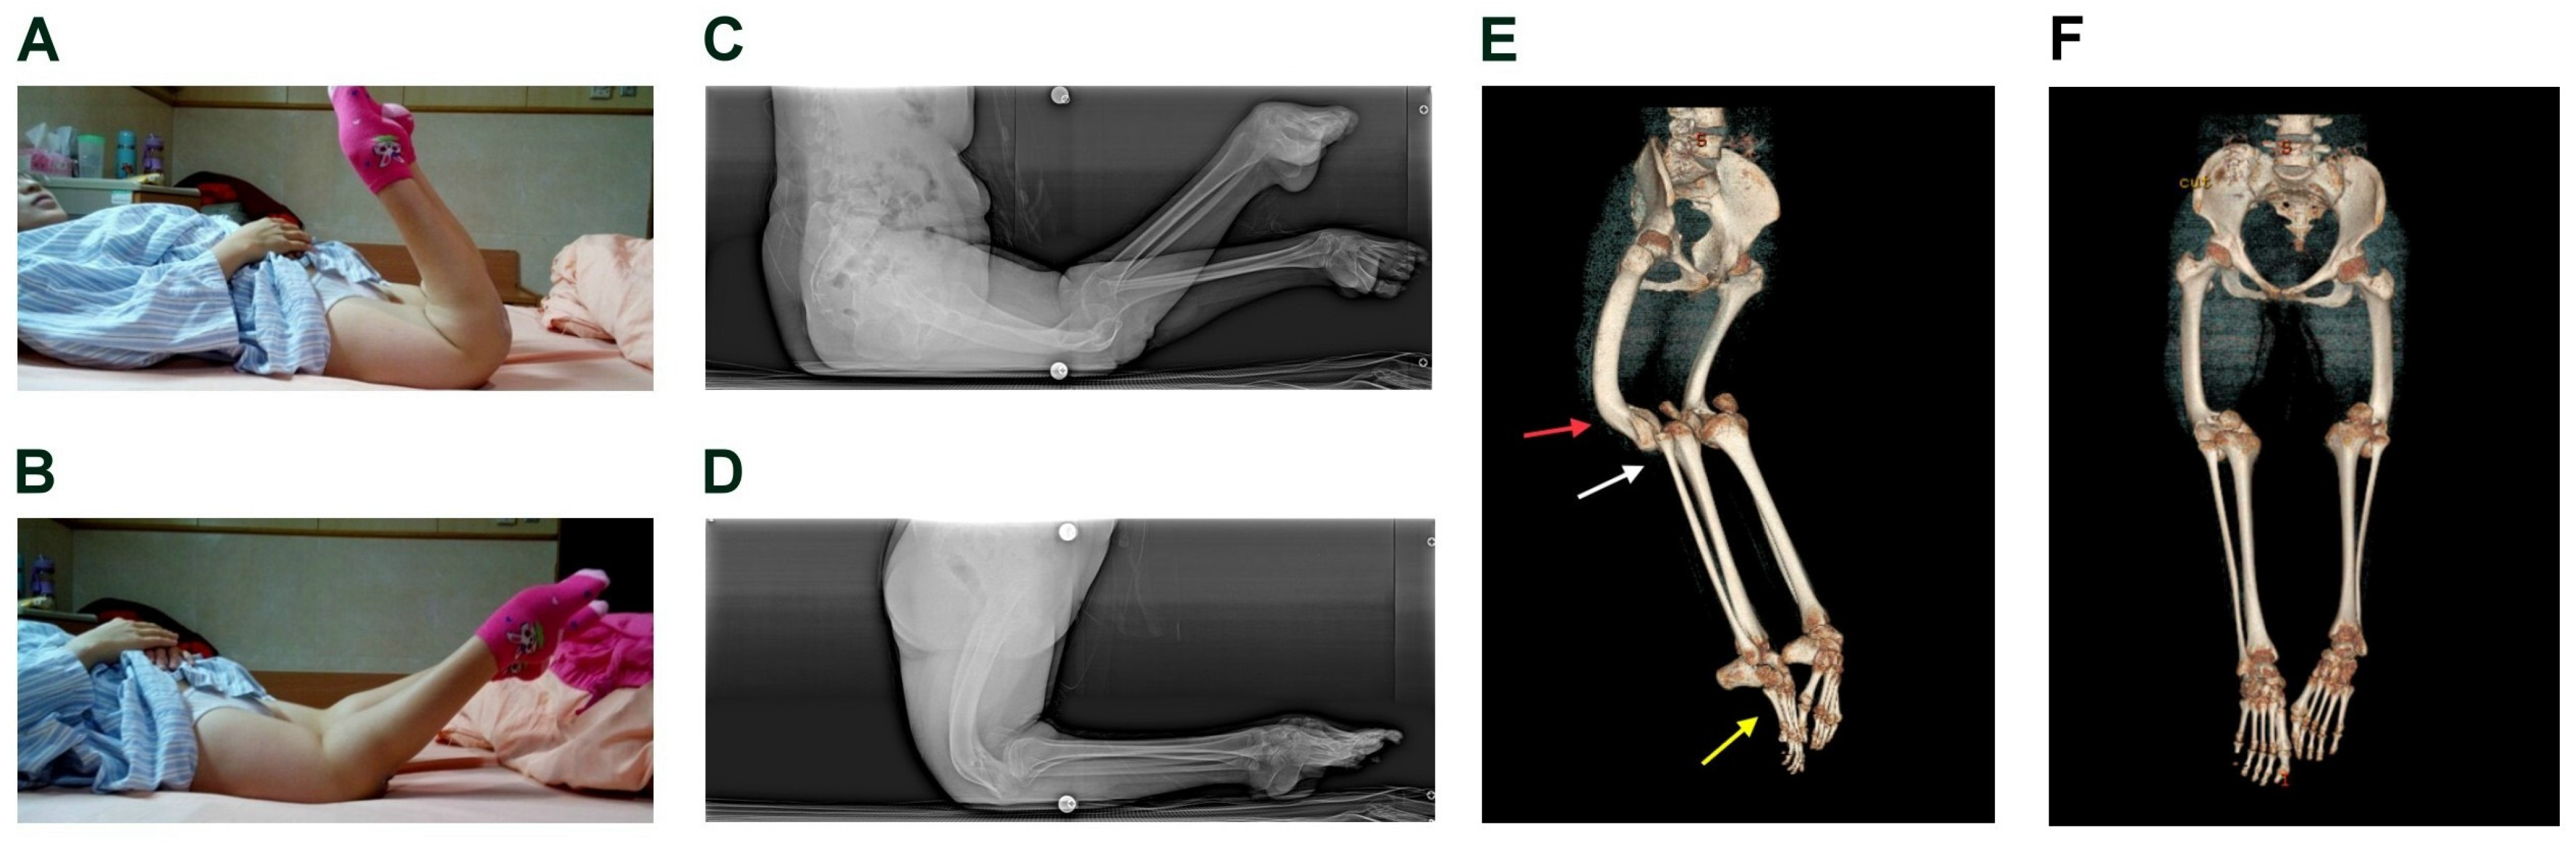

2.1. History and Presentation

2.2. Physical Examination and Pre-Operative Image Findings